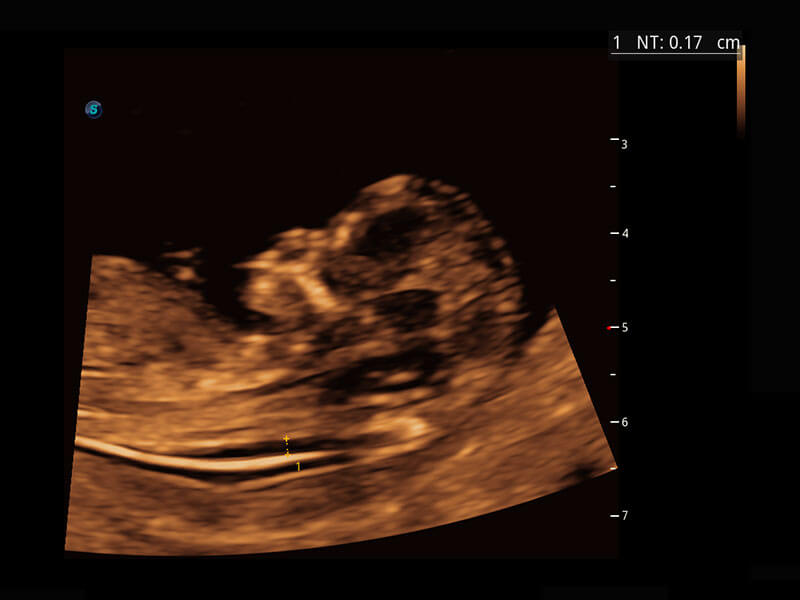

P60在胎儿早孕期超声筛查中为您带来优异的图像质量。

早孕-胎心

胎儿体循环